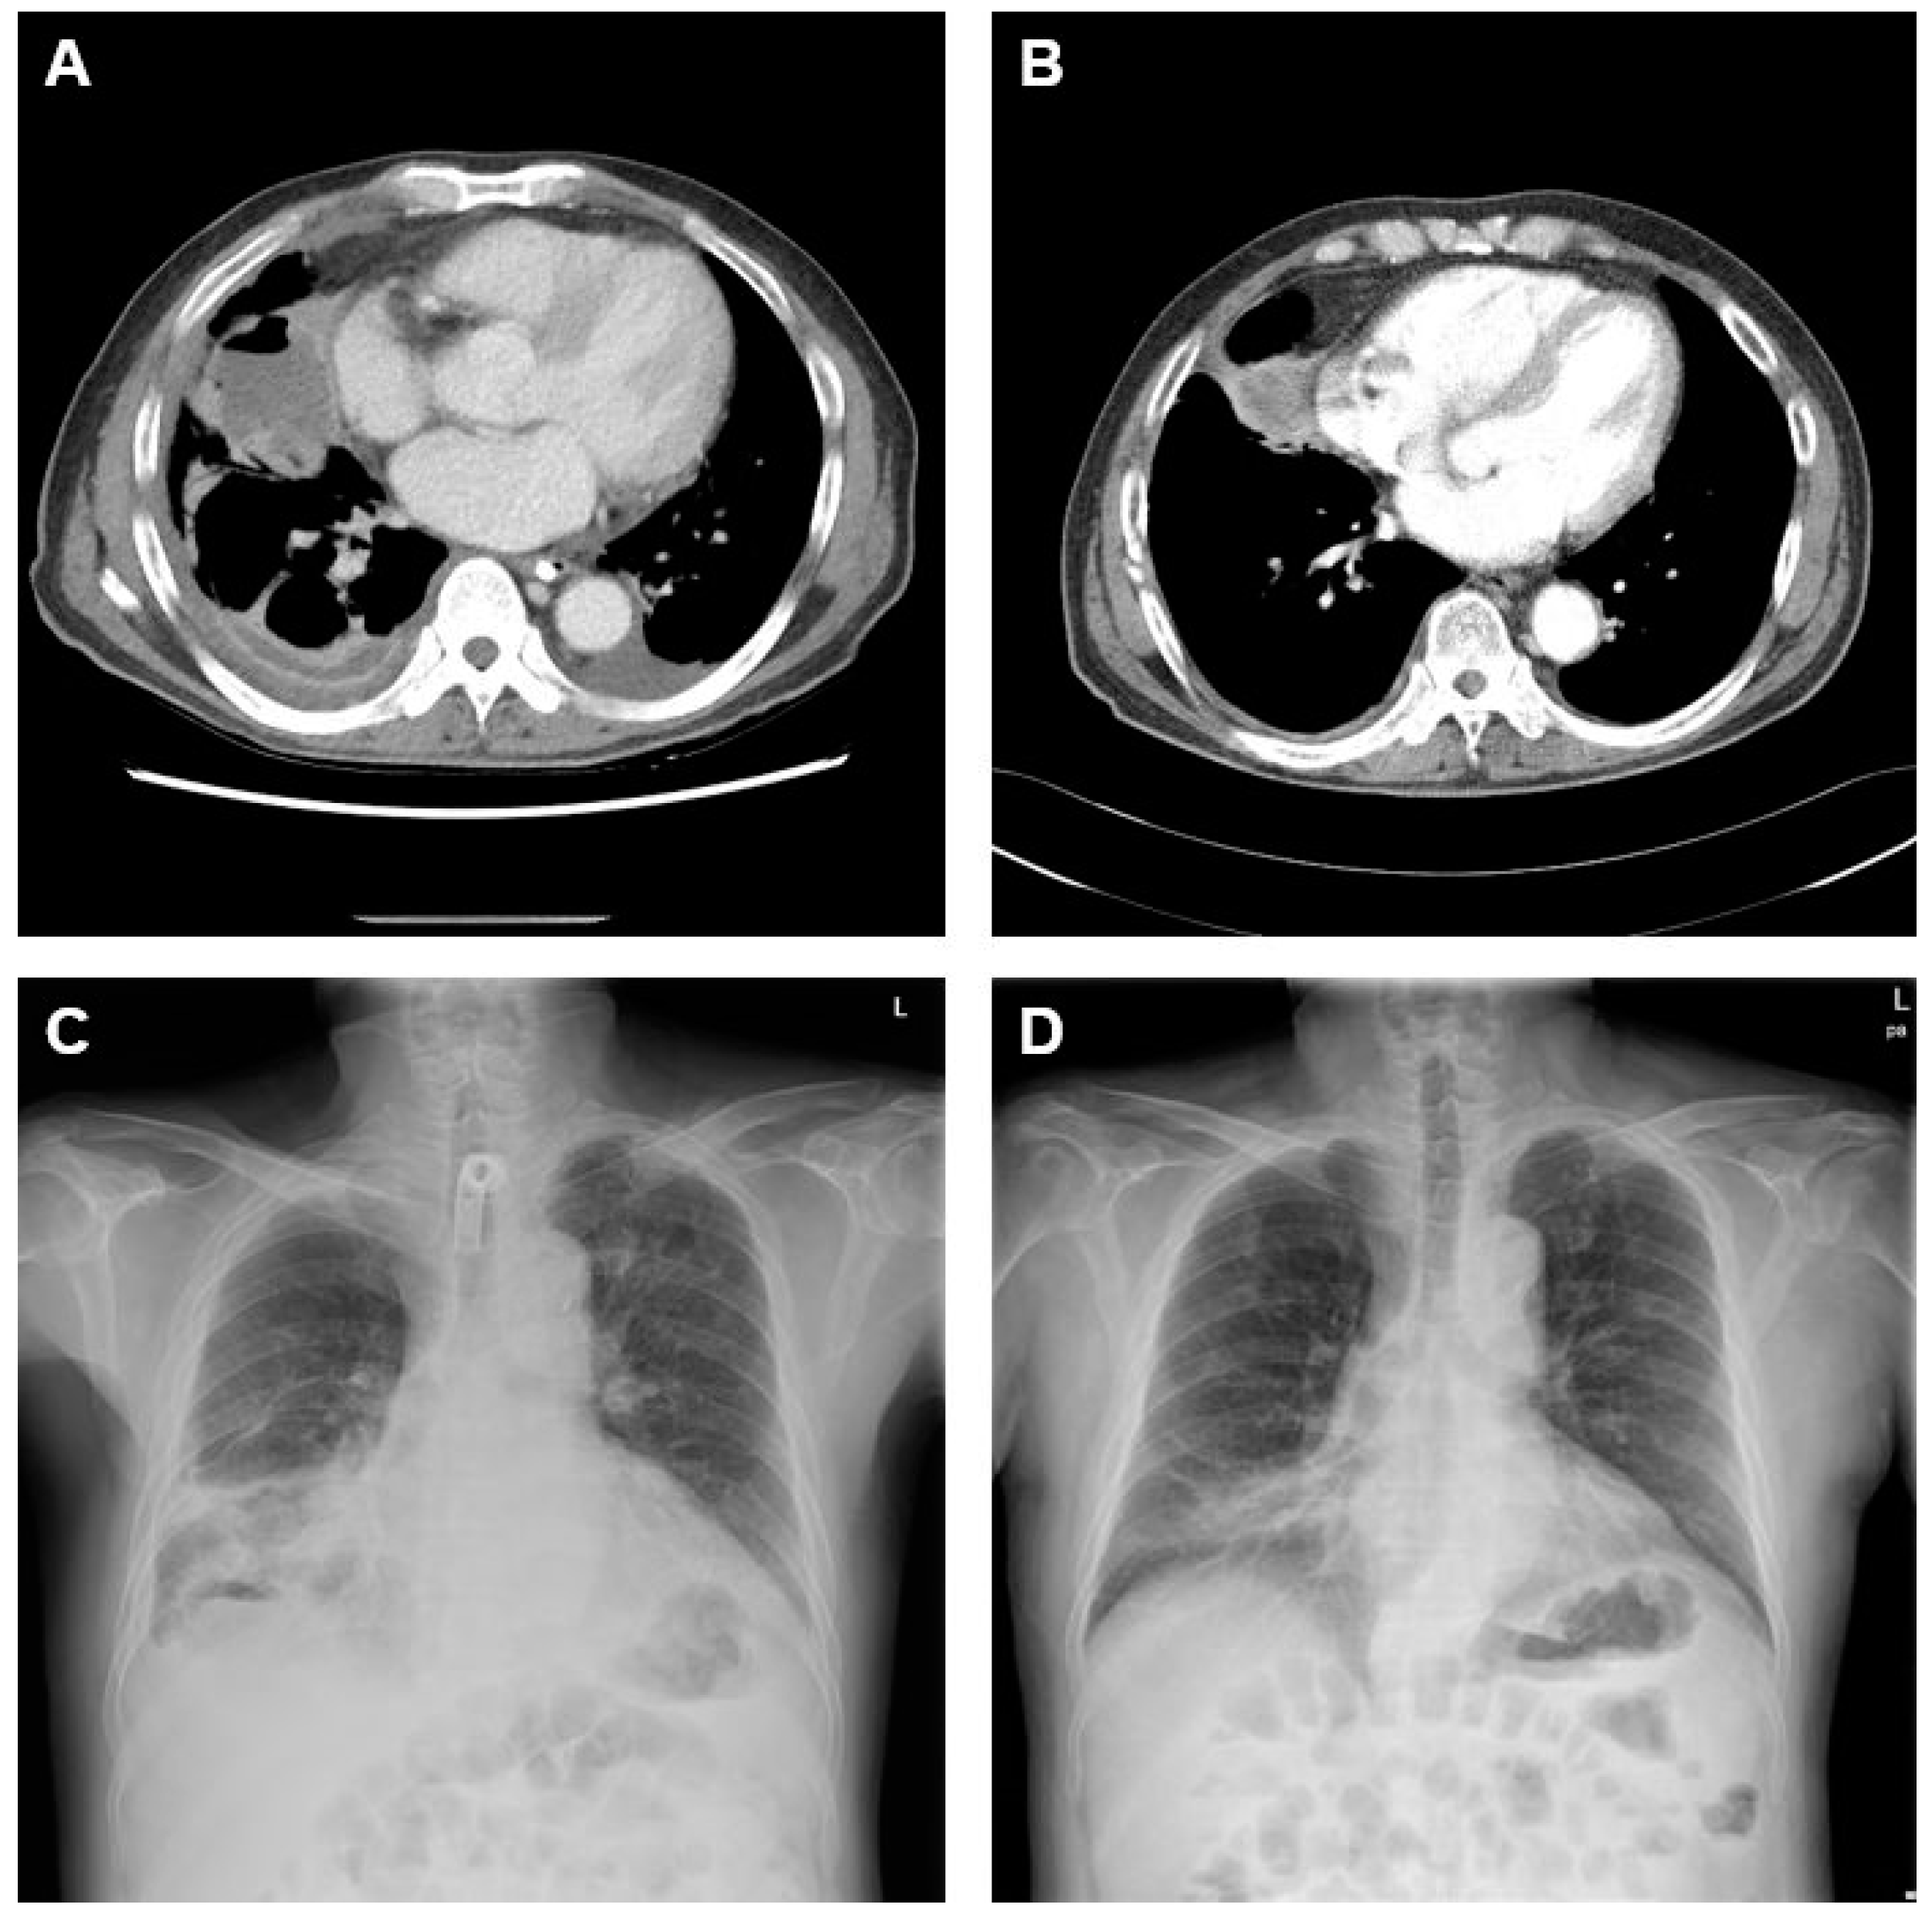

2. Case Presentation